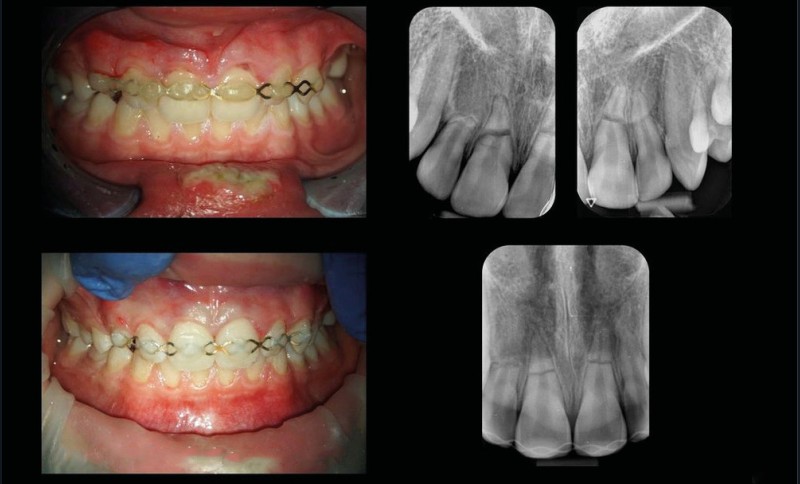

La fig. 1 montre la situation clinique le jour du traumatisme. Les photographies et radiographies permettent d’observer des factures radiculaires des 4 incisives ainsi que, au minimum, la luxation de la 11. Deux fractures radiculaires horizontales importantes au niveau de la 11 et de la 21 sont notées. Une fracture moins marquée radiologiquement au niveau de la 22 et une résorption apicale au niveau de la 12 sont visibles. Cette dernière est probablement antérieure au traumatisme du jour. Le patient est d’abord pris en charge par un dentiste de garde qui pose une attelle (fig. 2). Il est ensuite référé pour une prise en charge en endodontie.